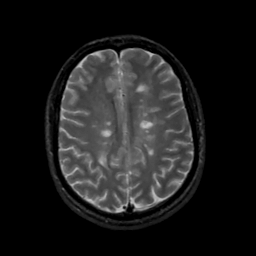

MR Study #12, May 12, 1991 -- Slice #34